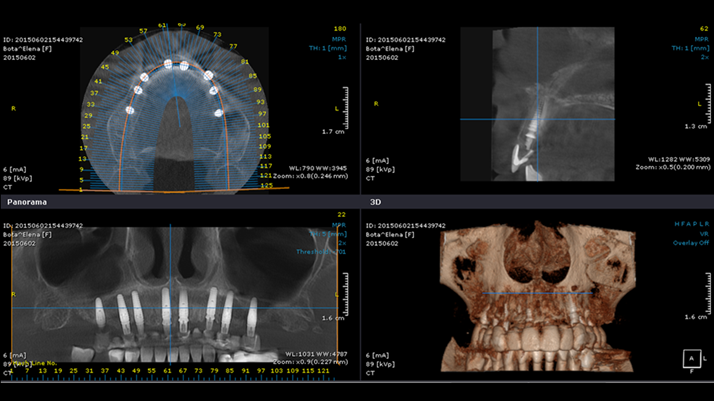

Clinical case: Extraction of all teeth in upper maxilla,

immediate implant placement, & provisionalization

- Courtesy of Dr. Iulian Filipov, Romania -

Keywords

AnyRidge, immediate placement, immediate provisionalization, maxillary fully edentulous case, initial stability, edentulous, Dr. Iulian Filipov, R2GATE, MEGA ISQ

Products:

AnyRidge implant system, Mega ISQ, R2GATE

“AnyRidge ensures long-term biological stability

& functionality even in

full-mouth rehabilitation case. ”